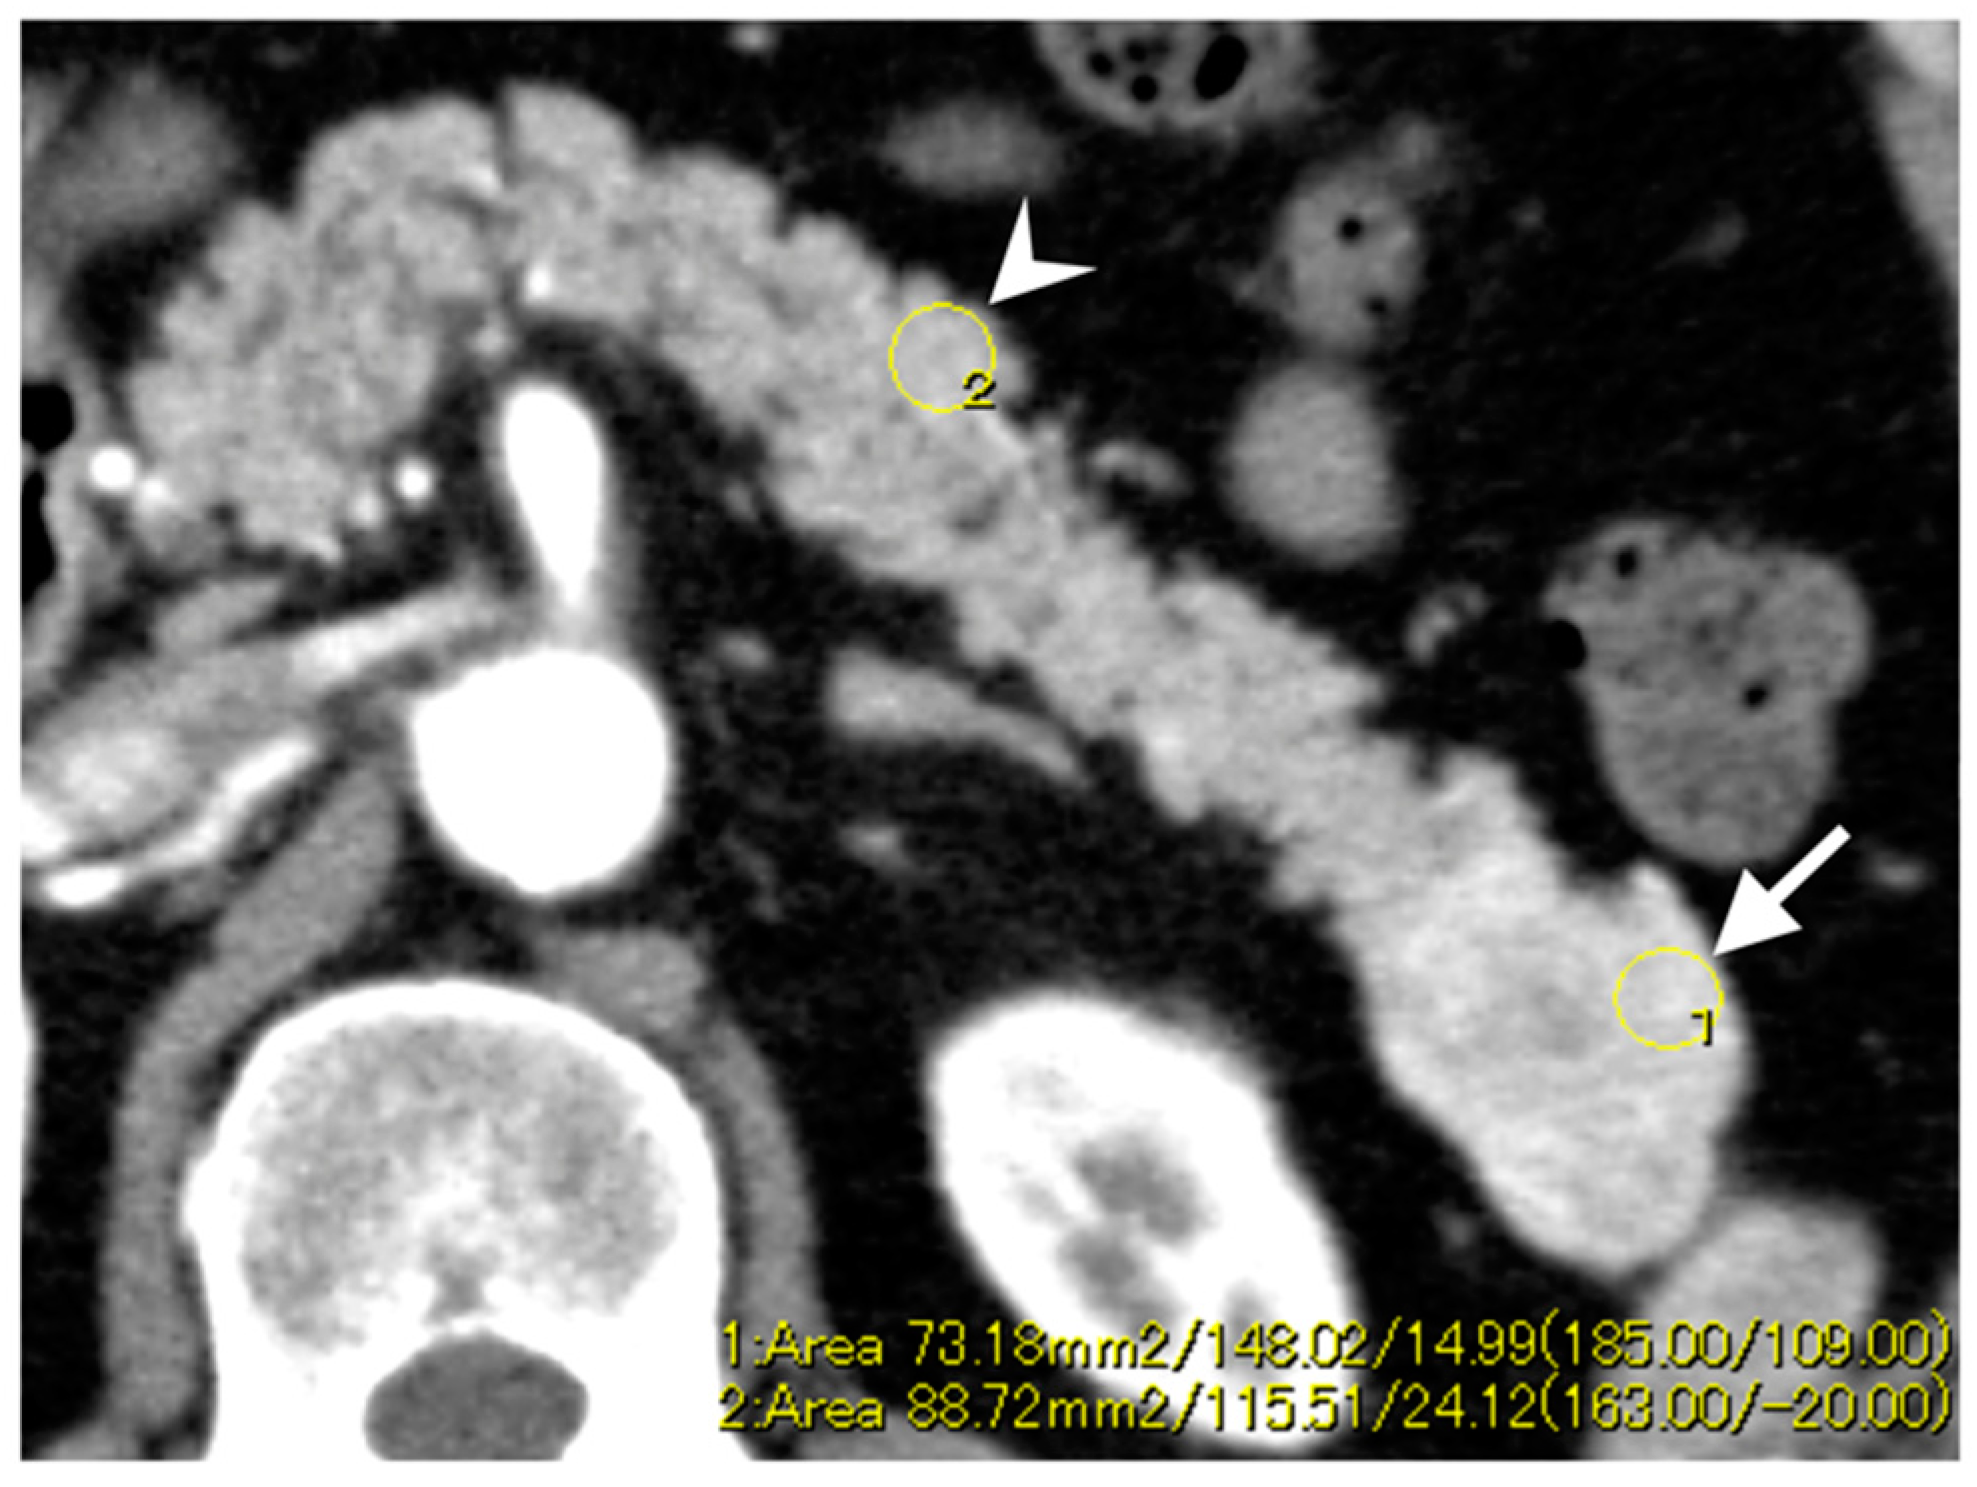

3.3. Enhancement Patterns of Pan-NENs Related to Low or High PAX6 Expression

| Enhancement ratio c | ||||

| Arterial phase | 1.19 ± 0.44 | 1.38 ± 0.36 | 0.28 | |

| Portal phase | 1.12 ± 0.28 | 1.30 ± 0.22 | 0.044 |